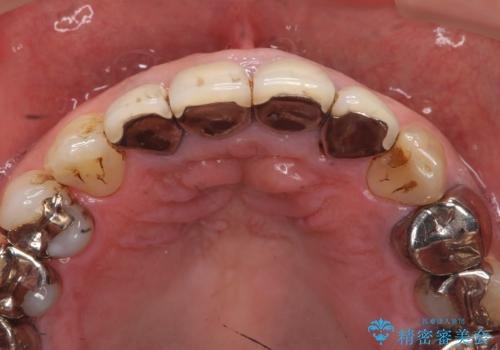

- 10数年前に治療した上顎前歯のクラウンをやり替え、審美性を回復したいと希望され来院されました。

X線写真より問題のなかった根管治療は行わず、クラウンを除去し仮歯でを装着したのちジルコニアクラウンを製作していきます。

失活歯の治療について

神経をすでに取られている歯の治療を行う場合、コアを除去したのちの再根管治療を行う場合とクラウンのみやり替えする場合、状況に応じて適切な治療をご提案いたします。